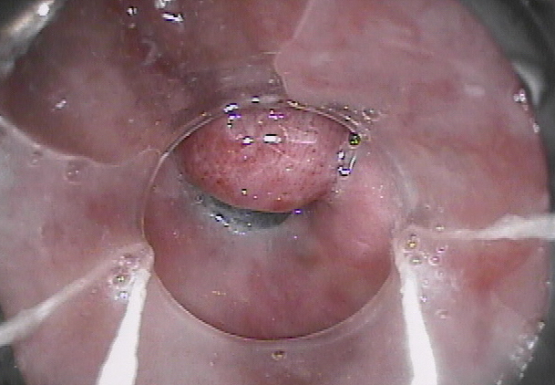

Endoscopic image after performance of splenectomy. Complete disappearance of the varices of the fundus of the stomach (Courtesy Dr. V. Penopoulos)